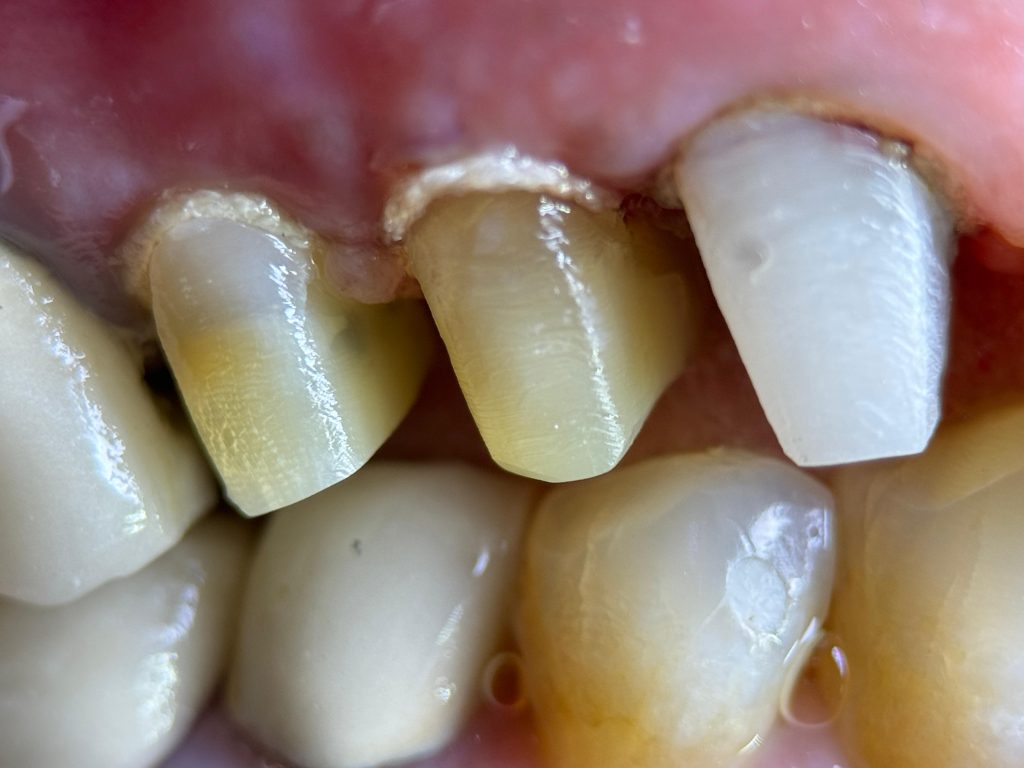

A middle-aged patient presented with the complaint of food impaction and sensitivity in the upper left posterior quadrant. Clinical examination revealed:

- Defective old composite and amalgam restorations

- Leaking margins and plaque retention zones

- Discolouration and structural weakness

- Localised tenderness on biting

- Short clinical crowns

Restorative status: compromised coronal seal and subgingival margins

DEEP MARGIN ELEVATION (DME)

Subgingival distal margins were identified in UL6 and UL7. To avoid crown lengthening surgery and preserve periodontal architecture, Deep Margin Elevation (DME) was performed:

- Rubber dam inversion achieved for moisture control

- Sectional matrix band adapted

- Adhesive protocol followed

- SDR bulk flowable composite layered to elevate the margin supragingivally

- This allowed controlled impression, better crown fit, and long-term periodontal compatibility